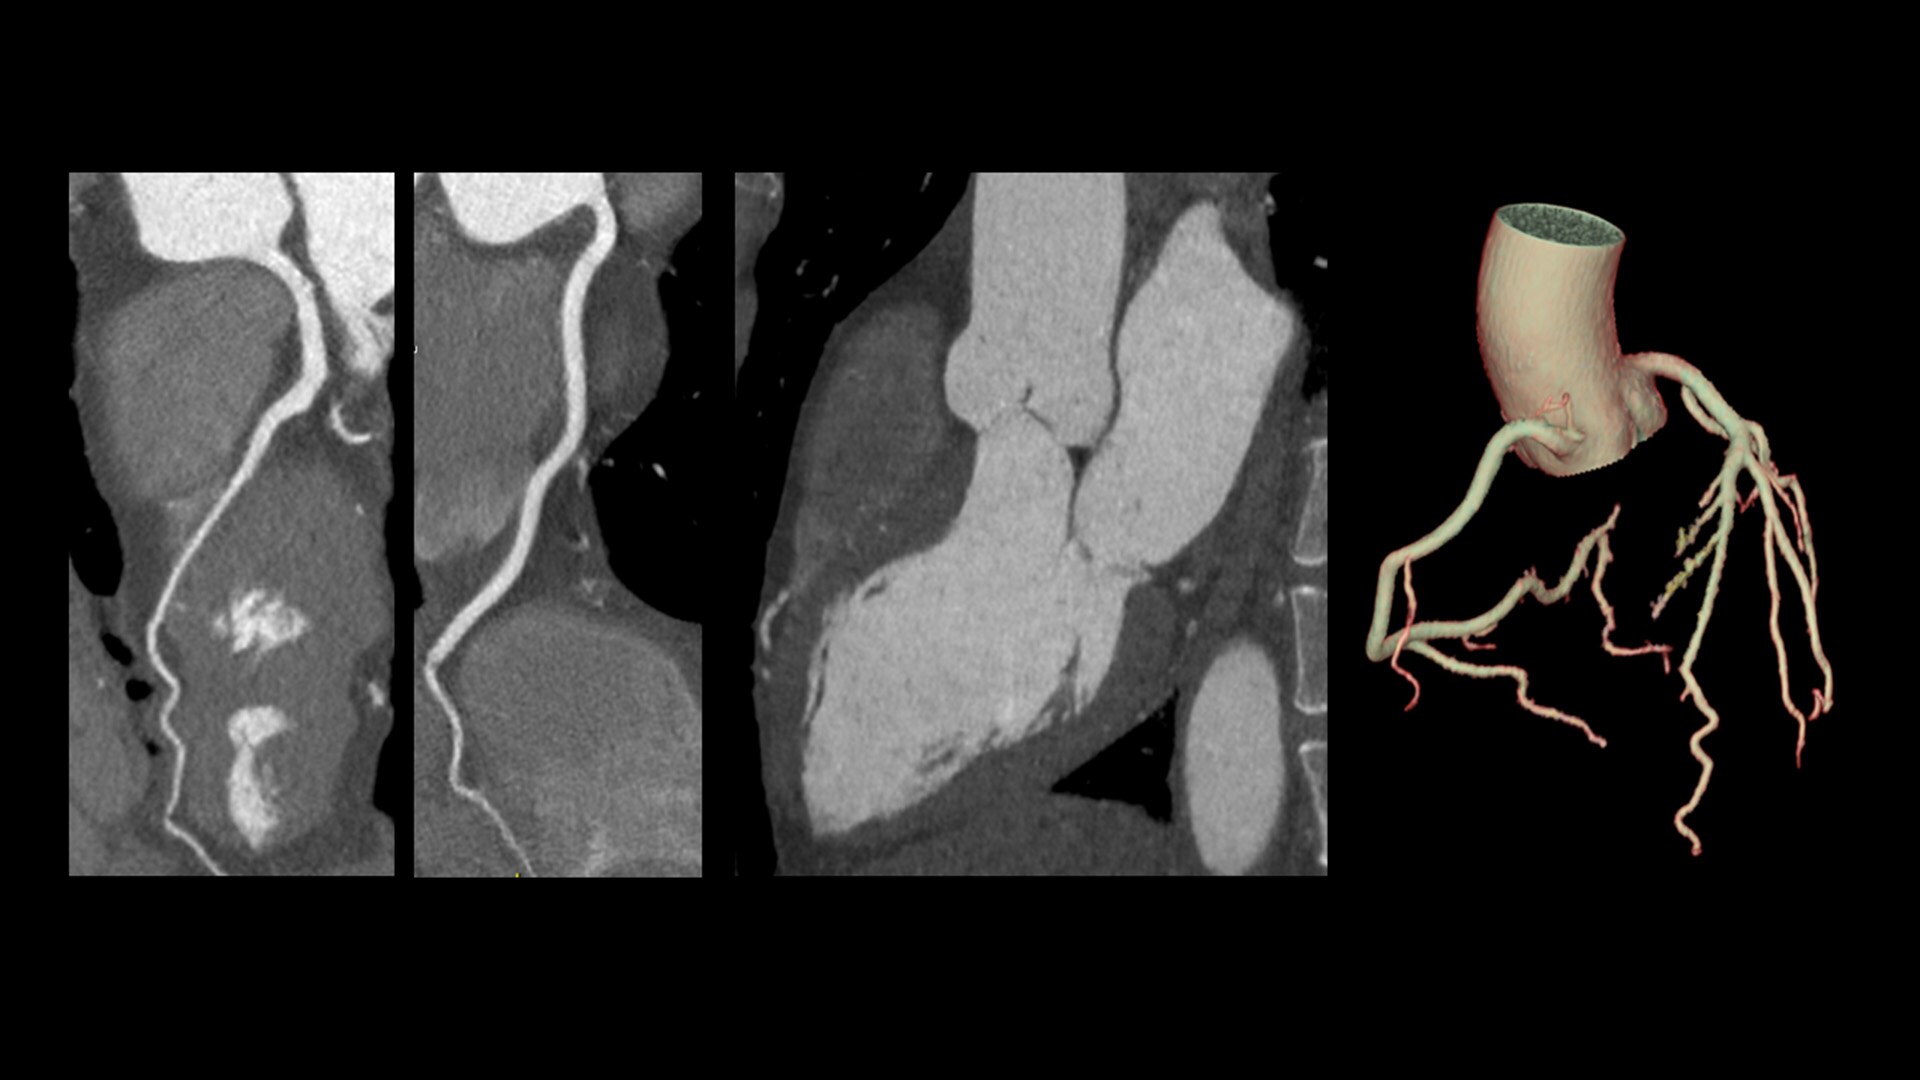

Unlimited 1-Beat Cardiac is designed to provide consistent, high-quality imaging for accurate diagnoses, even in challenging patients with atrial fibrillation, breath-holding difficulties, heavily calcified coronaries, in-stent restenosis, and situations where an ECG trace is unavailable.

Revolution Vibe's AI-powered workflow streamlines the entire cardiac CT process, from pre-scan to post-scan. It delivers accurate, automatically personalized scans for each patient, reducing dependency on user experience and enabling your team to achieve confident results swiftly.